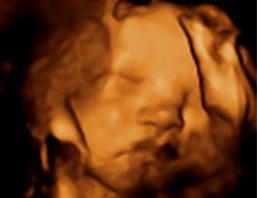

Semana 27 de embarazo: pruebas diagnósticas

Es buen momento para realizarte una ecografía en tres dimensiones, ya que es cuando mejor se puede visualizar el feto: tiene el tamaño y el líquido amniótico adecuado. Esta prueba es opcional, ya que sólo se realiza en los hospitales públicos para completar el estudio fetal, concretamente cuando se diagnostica una anomalía congénita en el feto al realizar la ecografía en 2D. En el resto de los casos, las parejas se hacen esta ecografía en centros privados para tener un recuerdo de su hijo.

La ecografía 3D es la imagen quieta e instantánea del feto en tres dimensiones. Hablamos de ecografía 4D a la ecografía 3D en movimiento, a modo de vídeo. Es importante que sepas que en muchos centros donde realizan ecografía 3D, los que las hacen no son ginecólogos ni radiólogos, no adjuntando por tanto, ningún informe escrito sino solo el CD con las fotos de tu hijo.

La ecografía 3D tiene mucha utilidad en el diagnóstico de malformaciones faciales con el labio leporino. También en alteraciones de las manos, pies, brazos y piernas. Por eso ante una sospecha de alguna de estas malformaciones con la ecografía 2D, se aconseja completar el estudio con una eco en tres dimensiones.

Ecografías de la semana 27 de embarazo

Ecografía semana 27: cara en 3D. La fisionomía de este bebé puede adivinarse mediante esta imagen en tres dimensiones.